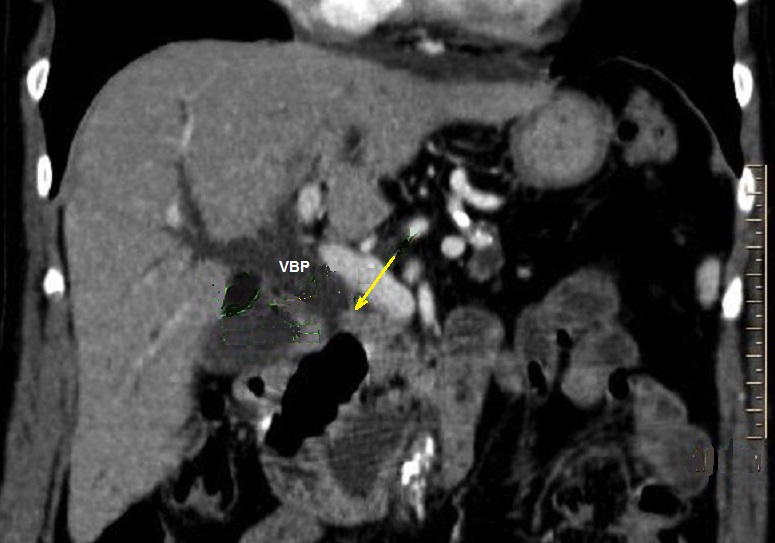

Image radiologique TDM d'unr

adenocarcinoma de la tete du pancreas en coupe

coronal avec contrast intraveineuse . Aspect

radiologique de l'obtacle tissulaire isodense a la

tete du pancreas ( fleche jaune ) et image de

dilataton marque de vopie biliaire principale ( VBP

) . |

Image

radiologique de dilatation du VBP et des voies

biliaire intrahapatique d'une tumeur de la tete

dupancreas . Coupe TDM axiale . |

Image de distention legere

de la vesicule biliaire ( VB ) et de voie biliaire

principale ( VBP ) . |